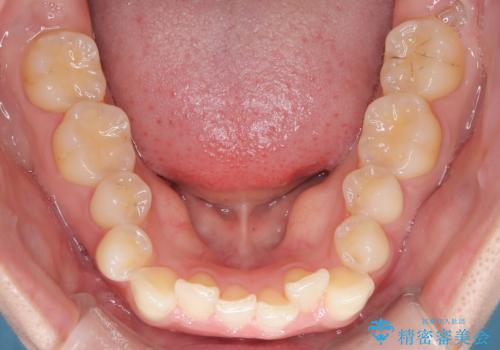

- 前歯のガタガタが気になるとのことでご相談いただきました。診察すると、歯列のスペースが不足し、前歯が重なっている状態でした。抜歯をせずに整えるため、歯と歯の間をわずかに削るIPR(歯列幅径削除)と、奥歯を後方へ動かす遠心移動を組み合わせてスペースを確保しながら並べる治療計画を立てました。

インビザラインを用いて歯を少しずつ移動させながら、IPRで微調整を行い、スペースを確保しました。また、奥歯を遠心移動させることで、前歯を自然な位置に並べることができました。治療後は、「ガタガタがなくなり、スムーズな歯並びになった」と患者様にもご満足いただきました。